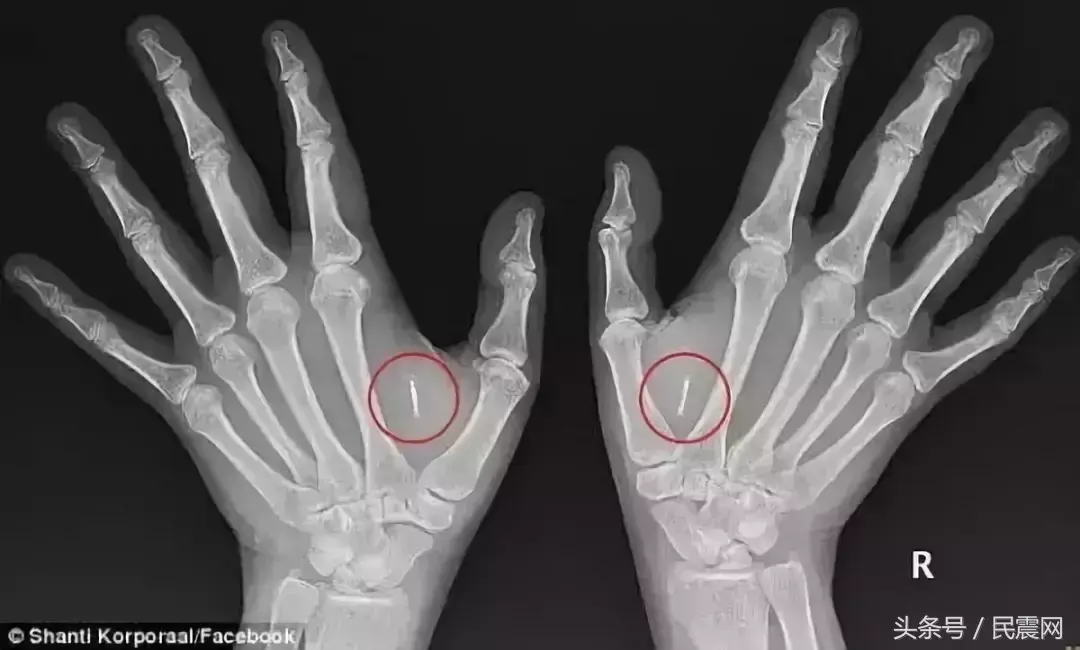

(图片:据每日邮报报道,澳洲女子Shanti Korporaal想过上一种富有科幻电影般的生活,她将双手植入了微型芯片,现在最常用到的就是无钥匙开门,免密开机。)

这里有张图,关于芯片如何移植的,

也就是说,芯片移植到手掌里,到时候干什么刷手就可以了。

这家美国公司是专门为Break Room(员工休息室)提供科技设备的公司,芯片使用的是RFID技术,移植过程很简单,

把右手虎口处的皮肤提起来,对准注射一下,不到一秒,就好了。